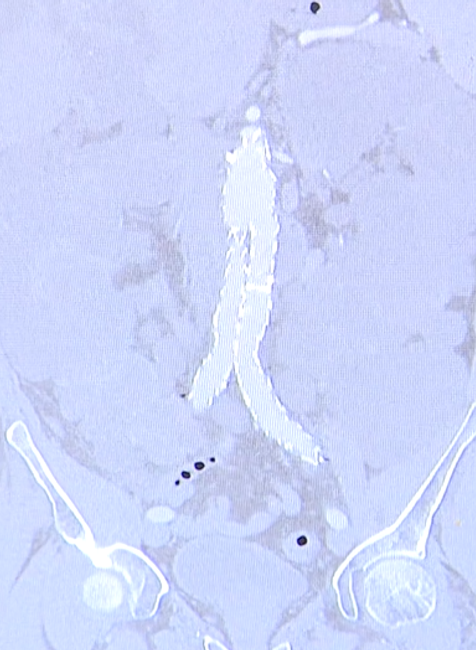

BRATISLAVA / Nevedeli zohnať pre svojho pacienta hotovú protézu z hovädzieho osrdcovníka, ktorá sa vkladá do ciev a tak si ju na sále na mieru pred operáciou ušili sami. Hovoríme o cievnych chirurgoch z bratislavskej univerzitnej nemocnice v Petržalke, ktorí majú v tomto na Slovensku prvenstvo. Pomohli tak mužovi, ktorý mal výduť v brušnej tepne a hrozilo prasknutie. Vlastnoručne ušitou protézou nahradili umelú výstuž, na ktorej sa objavila infekcia.

V brušnej cieve pacienta už bola umelá výstuž, ktorá zabezpečovala, aby mu výduť v cieve nepraskla, no tá sa mu infikovala a museli ju vymeniť za inú. Čo nie je častý no vážny stav a vtedy treba hľadať iné možnosti. "Musí sa odstrániť a musí sa nahradiť niečím, čo je rezistentné, to znamená, že nie je vnímavé na infekciu. Všetko prírodné je v poriadku," opísal Roman Slyško, primár oddelenia cievnej chirurgie v Nemocnici sv. Cyrila a Metoda.

Tu ale narazili na problém. "Do Európy sa prestali dovážať vytvárané protézy z hovädzieho osrdcovníka, ktoré boli extrémne drahé," uviedol Slyško. A tak si povedali, že si objednajú takýto čo najväčší kus vyrobený na takéto účely z hovädzieho osrdcovníka, ktorý zmerali, označili si a ušili. Celé to trvalo asi 20 minút a funkčná protéza bola hotová. "Vytvorenie tohto graftu som tvoril prvýkrát v živote. Na svete je publikovaných len nejakých 48 prípadov takéhoto samostatne chirurgom vytvoreného materiálu," dodal Slyško.